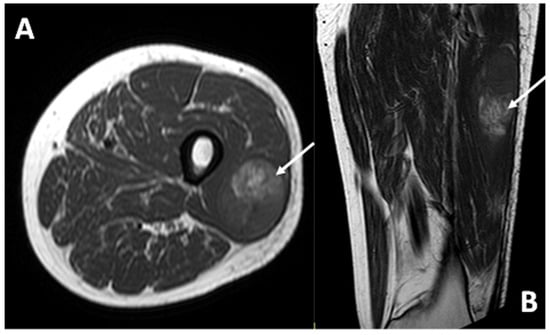

3.4. MRI Features

3.4.1. General MRI Features

3.4.2. Peritumoral Edema

3.4.3. Other MRI Features